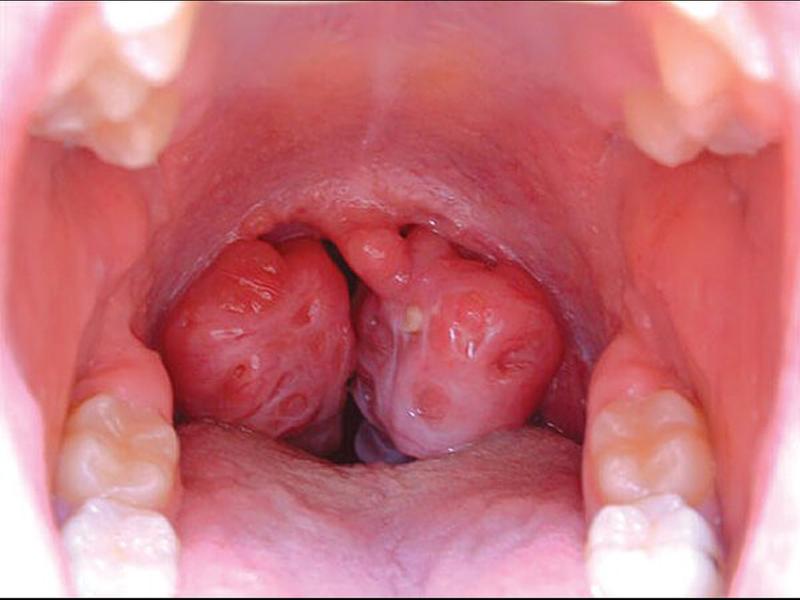

Ung thư vòm họng hay còn được biết tới là ung thư biểu mô vòm họng, là căn bệnh quái ác phát triển tại vùng vòm họng. Hầu hết các tế bào ung thư phát triển ở vị trí phía sau vòm họng hoặc tại chỗ thắt vòm họng hoặc ở ngách hầu chiếm tới khoảng 50%. Đây là một loại ung thư thuộc nhóm bệnh lý vùng đầu cổ, có tốc độ phát triển rất nhanh chóng nếu không được phát hiện sớm và kiểm soát kịp thời, đúng cách.

Những ca mắc ung thư vòm họng ở trẻ em thường khó phát hiện hơn và rất dễ nhầm lẫn với các bệnh lý khác, đồng thời gây nên hậu quả nghiêm trọng cho sức khỏe của trẻ. Dưới đây là các triệu chứng ung thư vòm họng ở trẻ mà các bậc phụ huynh cần quan tâm:

Trẻ thường xuyên bị ngạt mũi và chảy nước mũi không kiểm soát mà không phải do bệnh lý cảm cúm thì đây chính là dấu hiệu cảnh báo đầu tiên của bệnh ung thư vòm họng. Tình trạng ngạt mũi hoặc chảy nước mũi chính là triệu chứng xảy ra ở giai đoạn sớm và thường xuất hiện ở một bên mũi. Tuy nhiên, nếu tiến triển nặng hơn với khối u đã gây chèn ép thì trẻ có thể bị ngạt mũi cả 2 bên.

Chảy máu cam không chủ đích cũng là một trong những triệu chứng báo hiệu bệnh ung thư vòm họng ở trẻ em. Chảy máu cam cũng có thể là biểu hiện của một số bệnh lý thông thường và các bậc cha mẹ thường chủ động cho trẻ sử dụng thuốc để điều trị triệu chứng này. Điều này sẽ khiến cho việc phát hiện bệnh ung thư vòm họng ở trẻ gặp khó khăn. Do vậy nếu thấy bé nhà mình chảy máu cam không rõ nguyên nhân và kéo dài thì cha mẹ nên đưa trẻ tới các cơ sở y tế uy tín để được thăm khám và kịp thời điều trị, đảm bảo an toàn tuyệt đối cho bé.

Khi các tế bào ung thư xâm lấn và lây lan với tốc độ nhanh chóng tại vị trí vòm họng thì có thể xuất hiện thêm những hạch nhỏ tại vị trí vùng cổ của trẻ em. Khi mới xuất hiện, hạch thường có kích thước nhỏ nên khó có thể phát hiện.

Tuy nhiên sau một khoảng thời gian dài thì hạch sẽ lớn dần và xuất hiện nhiều ở vùng cổ sau đó lây lan ra những vùng xung quanh. Đến giai đoạn hạch sưng to và nổi lên thì có thể sờ thấy nhưng không gây đau.

Ung thư vòm họng ở trẻ có thể xuất hiện triệu chứng ù tai ở một bên hoặc cả 2 bên tai, kèm theo đó là tình trạng thính lực bị suy giảm. Trẻ có thể bị đau nhức bên trong tai, nghiêm trọng hơn có thể xuất hiện dịch mủ có lẫn máu chảy ra từ trong tai. Đây chính là biểu hiện tai của bé đã bị hoại tử, rất nguy hiểm.